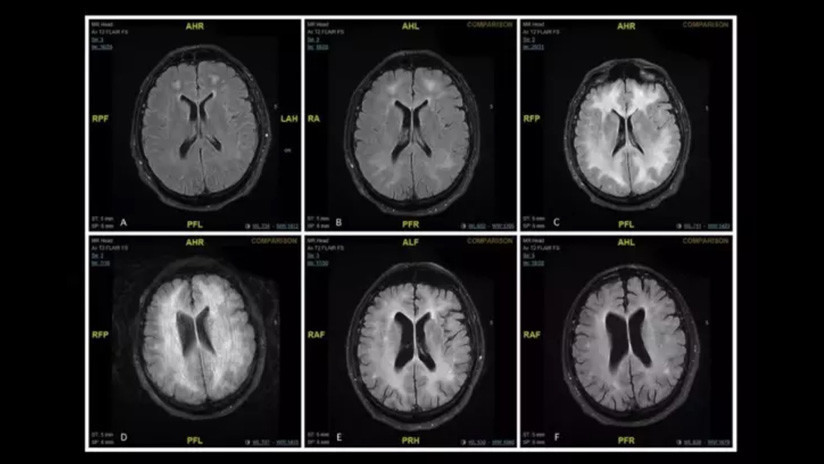

Las imágenes corresponden a un varón de 45 años que sufrió leucoencefalopatía inducida por la droga.

Después de diferentes exámenes, los especialistas determinaron que el hombre había sufrido un efecto secundario muy inusual, pero potencialmente peligroso, inducido por el narcótico y denominado leucoencefalopatía. De acuerdo con los médicos, el trastorno se puede presentar de distintas maneras, incluido un nivel alterado de la conciencia, confusión, lenguaje y visión alteradas, fiebre o espasticidad. Los registros de los escáneres mostraron la aguda degeneración de la materia blanca de su cerebro.

Tras dos semanas de tratamiento con esteroides, un intercambio de plasma y anticuerpos el paciente comenzó a mostrar mejoría y fue trasladado a una clínica de desintoxicación. Un año después, los exámenes determinaron que su capacidad cognitiva funcionaba de forma normal, aunque el cerebro seguía mostrando signos de los daños causados por la droga.